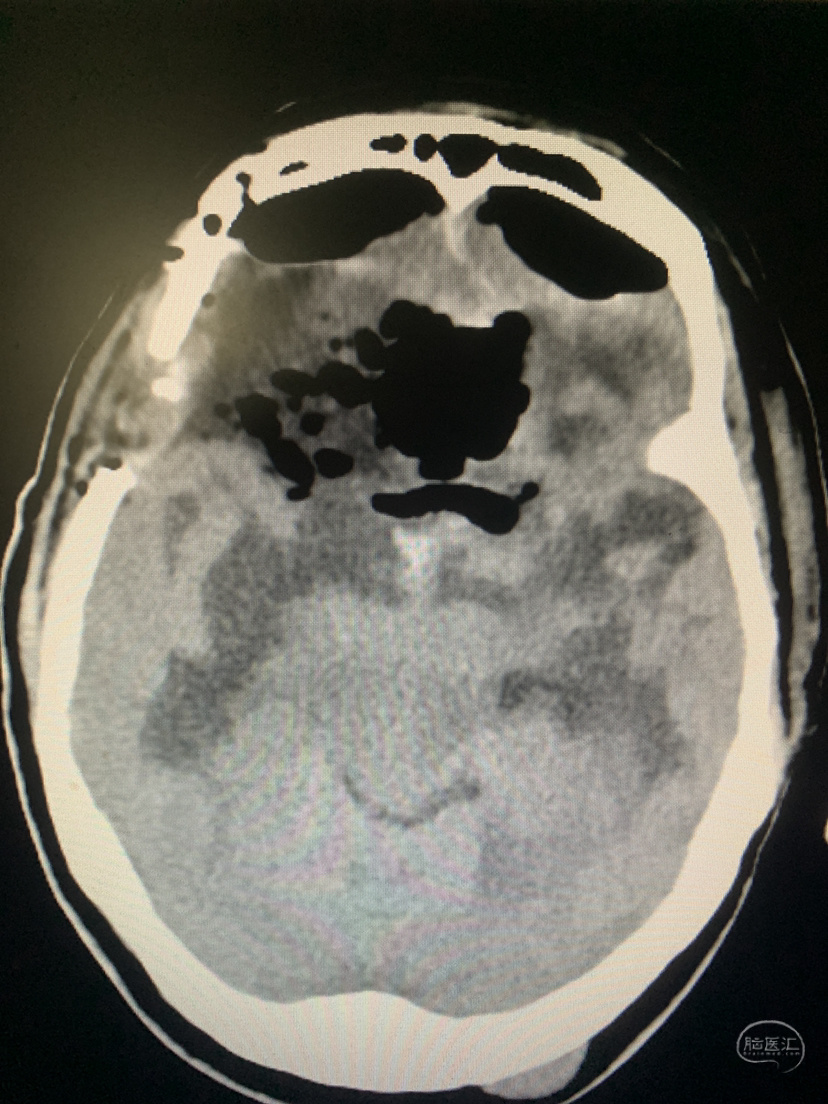

术前CT

术前CT